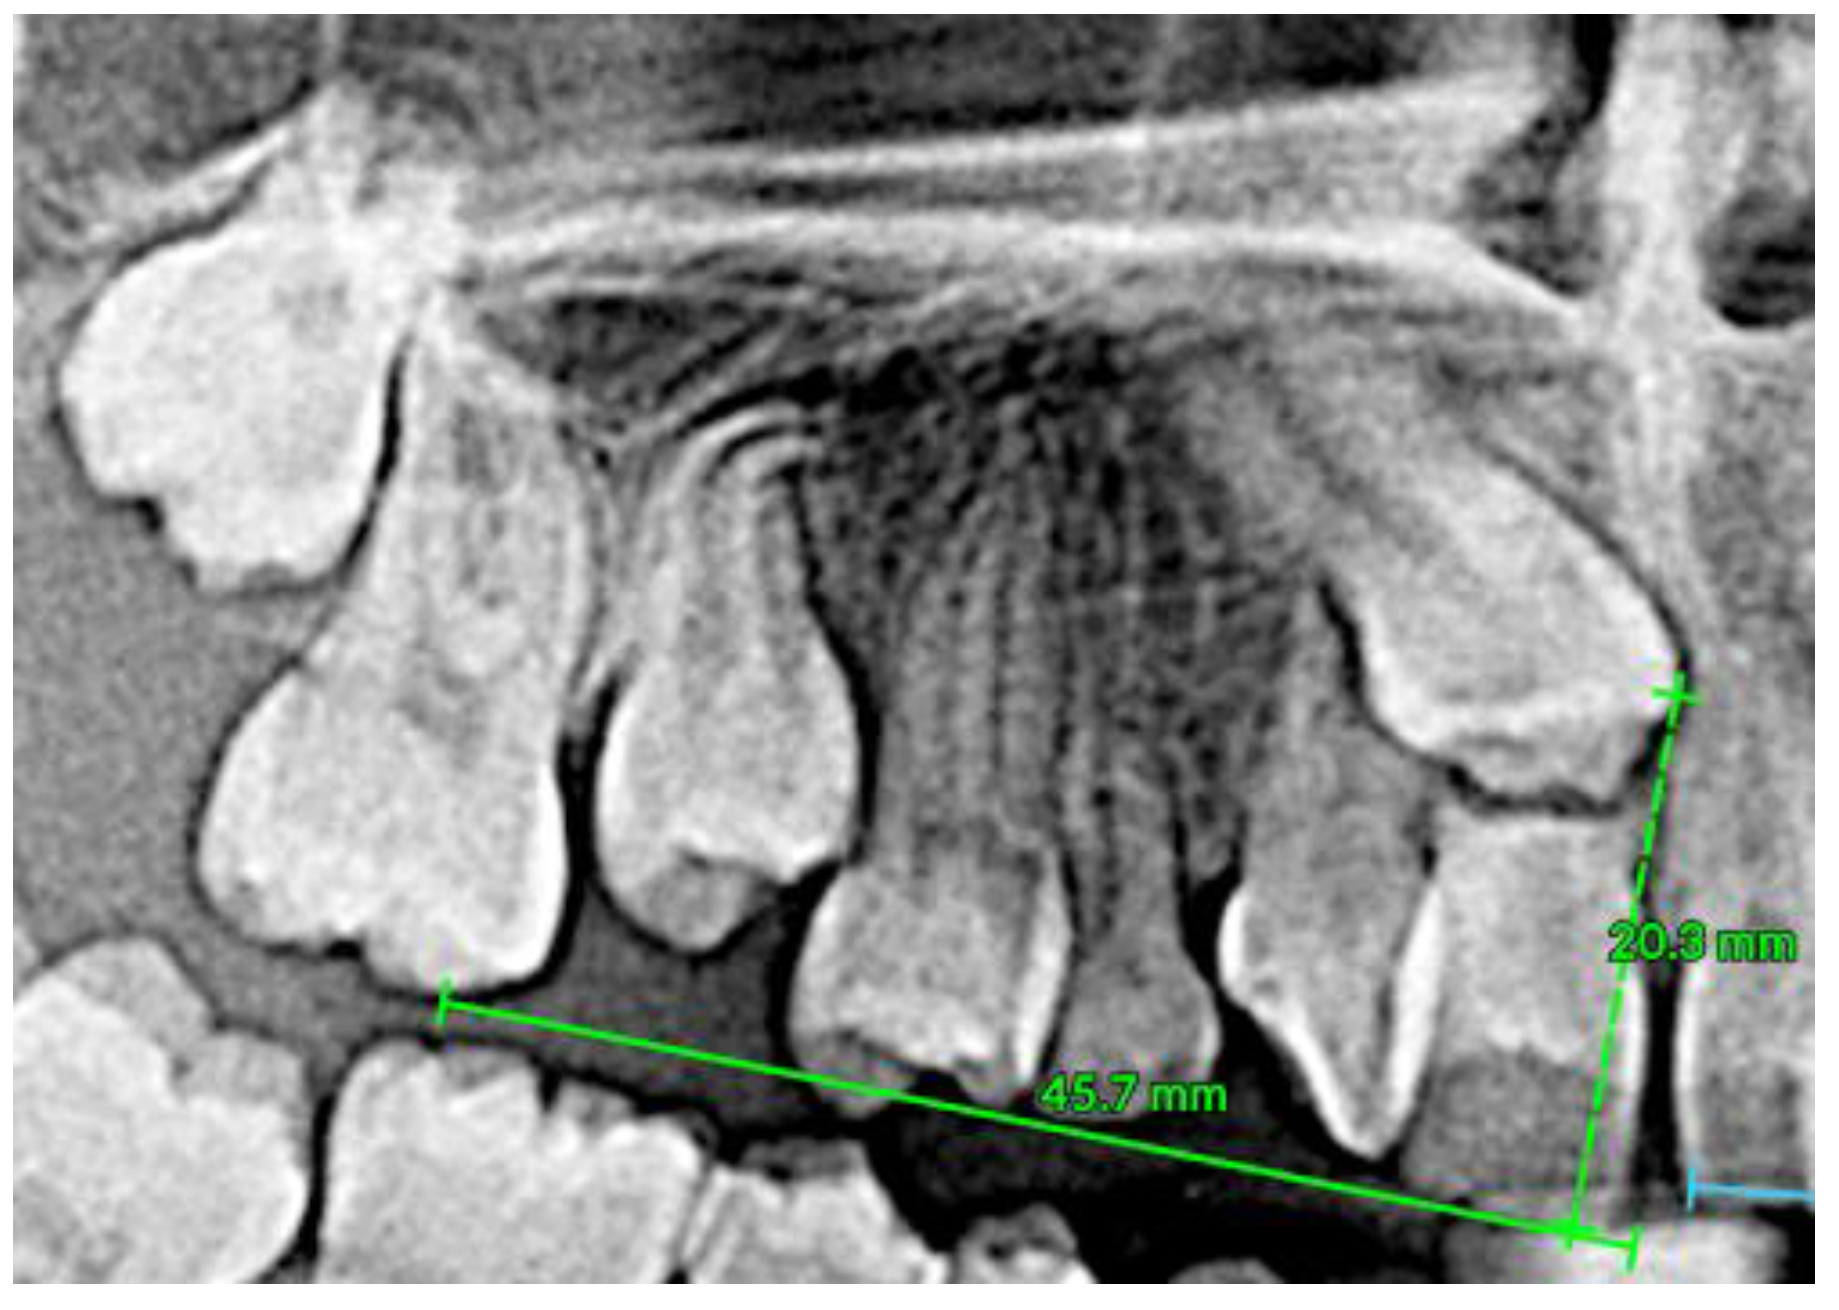

2.7. Clinical Case

| Pinho T., Amaral R. 2025 | ♀ 13 YO | Mx.C.I1 | C | R | V (impacted) | Cl I | Maintained | -Total root resorption of tooth #11 due to the position of the ectopic canine |

3.2. Clinical Case